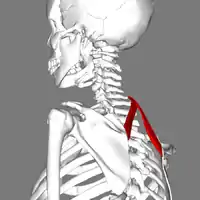

Origine

Son origine est tendineuse sur les processus épineux des vertèbres cervicales C7 et T1.

Trajet

Il se dirige obliquement et latéralement.

Vue latérale.